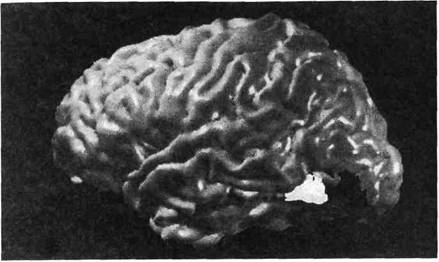

— Чувствую, как какой-то острый предмет передвигается через мизинец к ладони, — ответил он.

Повторяя эту процедуру, я обнаружил на его лице настоящую карту его отсутствующей кисти. Эта карта была потрясающе точной и целостной, с точно очерченными пальцами (см. рис. 1.1). Однажды я нажал на его щеку влажной ватной палочкой и пустил струйкой по его лицу капельку воды, как будто бы это стекала слеза. Он чувствовал, как вода стекала по его лицу, но заявил, что также ощущает, как капля стекает вдоль его фантомной руки. Правым указательным пальцем он даже проследил извилистый путь капли по пустому воздуху перед своей культей. Из любопытства я попросил его поднять культю и направить фантомную конечность на потолок. К его удивлению, он почувствовал, как следующая капля воды текла вверх по его фантому, отрицая закон силы притяжения.

Рис. 1.1. Пациент с левой фантомной рукой. Когда дотрагиваются до различных частей его лица, он ощущает прикосновения к различным частям фантомной руки. Р - ладонь, Т - большой палец, В - основание большого пальца, I - указательный палец

Виктор сказал, что никогда раньше не ощущал эту виртуальную кисть на своем лице, но как только он узнал об этом, то сразу нашел ей хорошее применение. Лишь только его фантомная ладонь начинает чесаться — что бывало весьма часто и буквально сводило его с ума, — он успокаивает ее, почесывая соответствующее место на лице. Почему так? Ответ, как я понял, можно найти в анатомии мозга. Вся поверхность кожи левой стороны тела отображена в виде карты на полосе коры, называемой постцентральной извилиной (см. рис. В.2), идущей вниз по правой стороне мозга. Эта карта часто изображается в виде схематического человечка на поверхности мозга (рис. 1.2). Хотя по большей части карта весьма точна, некоторые кусочки перепутаны по сравнению с тем, как реально тело устроено. Обратите внимание, что карта лица расположена рядом с картой кисти руки, а вовсе не шеи, где «должна» была быть. Это как раз и дало мне ключ к решению.